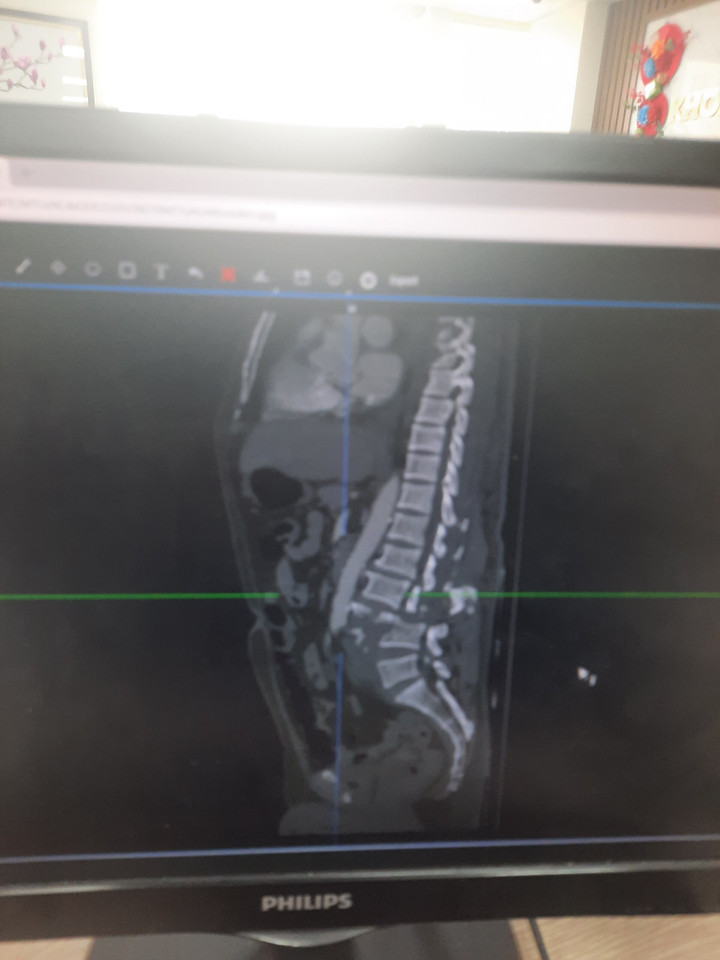

Hình ảnh phim chụp bệnh nhân gãy vỡ đốt sống L3,L4. (Ảnh: PV)

Bác sĩ Bính cho biết, trên hình ảnh phim chụp bệnh nhân bị vỡ hoàn toàn đốt sống thắt lưng L3-L4. Đây là chấn thương rất nặng, để lại di chứng liệt 2 chân.